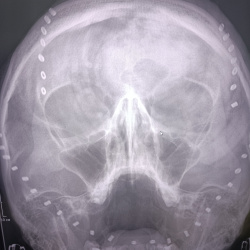

Здравствуйте, подскажите, женщина 36 лет, жалобы на умеренное болезненое образование лба слева. появилось примерно за последние 6 месяцев. чем это моожет быть? какой можно поставить диф ряд?

27.06.2024 - 07:16